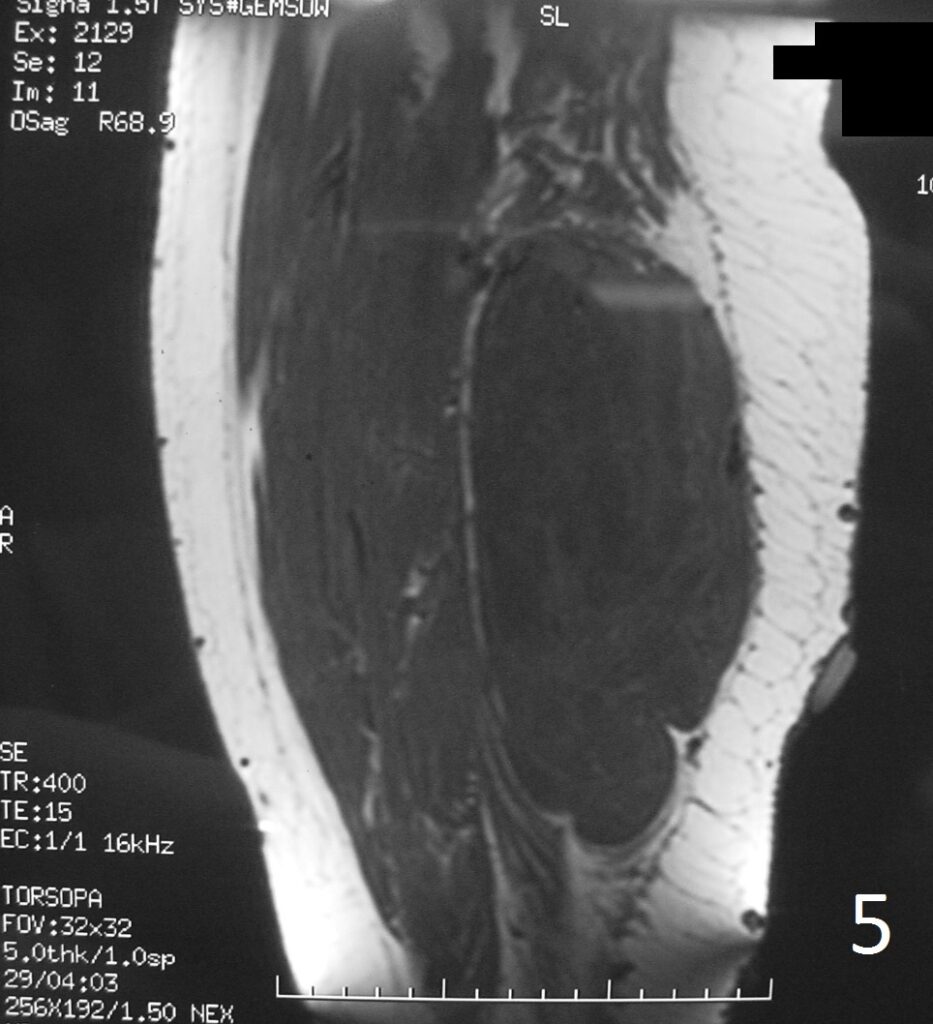

Fig 4-6: T2W FS demonstrates same features (Fig. 4) . Sagittal T1W (Fig. 5) and T1W FS (Fig. 6) of same case.